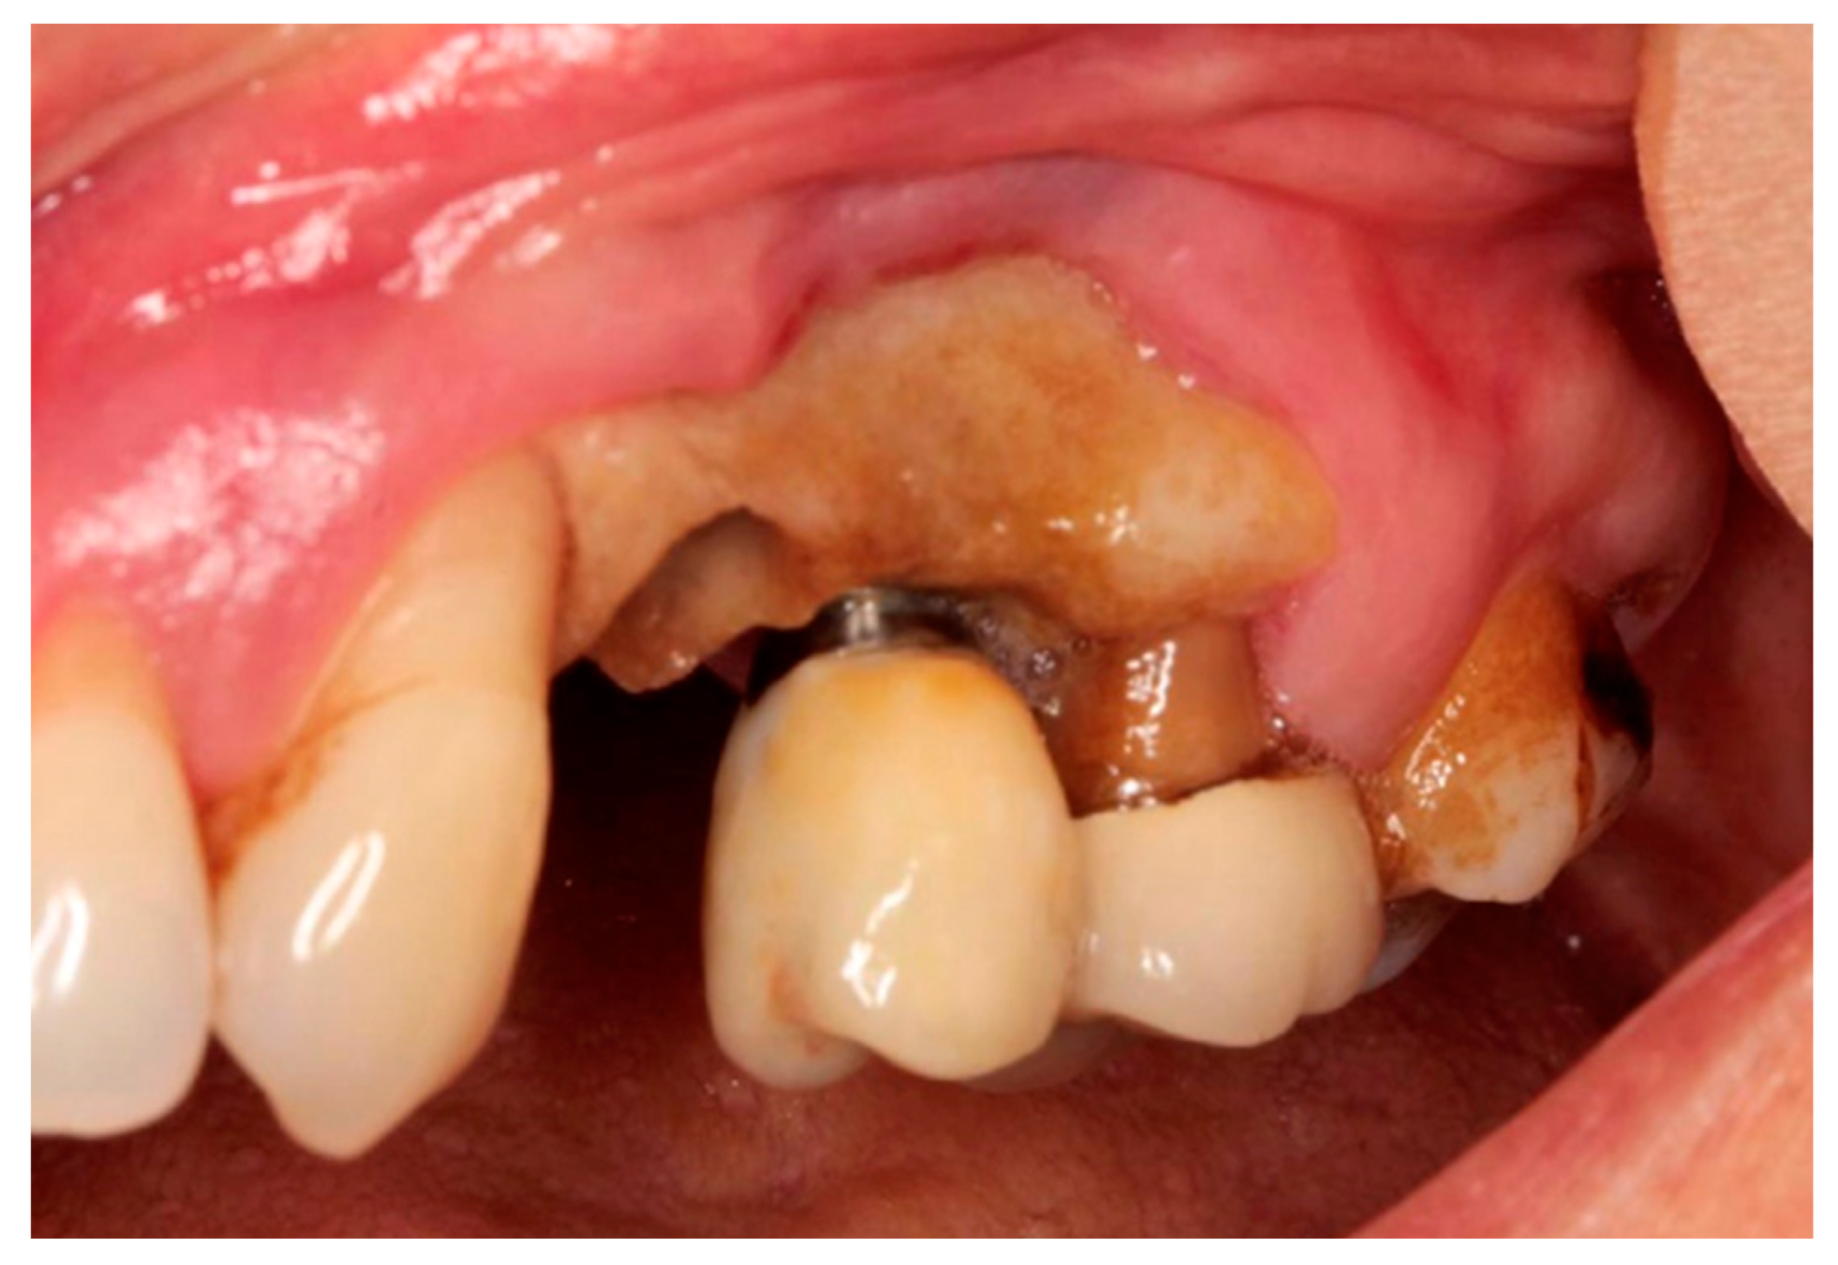

- Stage 1: Exposed and necrotic bone or fistula that probes the bone in asymptomatic patients with no evidence of infection/inflammation.

- Stage 2: Exposed and necrotic bone, or fistula that probes the bone, with evidence of infection/inflammation. The patients were symptomatic.